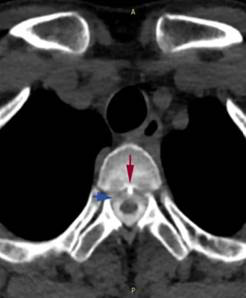

宋先生的脊柱磁共振检查可见第2、3胸椎之间有“骨刺”形成(红箭头)刺破硬脊髓膜,造成脑脊液外漏(蓝箭头)医院供图